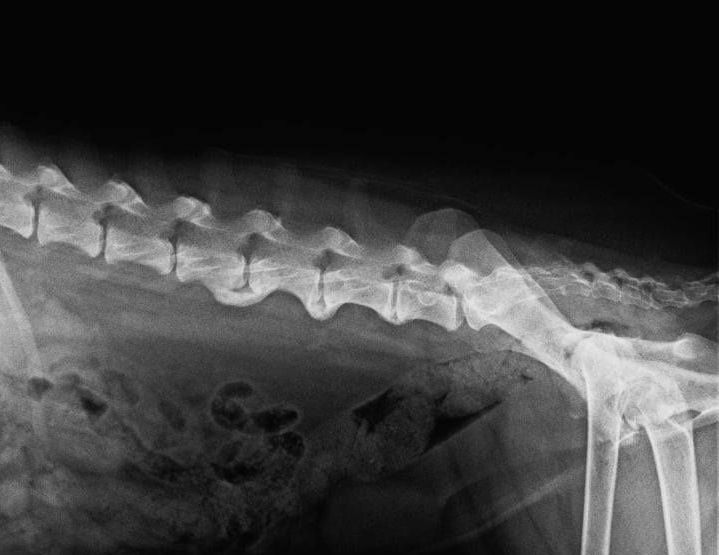

Die Ellenbogendysplasie beim Hund ist eine typische Wachstumserkrankung. Die ersten Symptome treten daher bereits im ersten Lebensjahr, häufig sogar in den ersten Lebensmonaten auf.

Es gibt verschiedene Formen der Ellenbogendysplasie beim Hund:

- Isolierter Processus Anconeus (IPA): hierbei wächst ein Knochenfortsatz der Elle, der Processus anconeus nicht an die Elle an. Der Processus Anconeus ist ein kleiner Knochenfortsatz, der an der Spitze des Ellenbogens liegt und für die Stabilität des Gelenks sorgt. Frakturen in diesem Bereich können zu Schmerzen, Schwellungen und eingeschränkter Beweglichkeit führen.

- Osteochondrosis dissecans (OCD): die OCD ist eine Erkrankung des Gelenkknorpels und des darunterliegenden Knochens bei Hunden. Hierbei kommt es zur Ablösung von Knorpel- und Knochenstücken im Gelenk, was Schmerzen, Entzündungen und Gelenkergüsse verursacht. Die betroffenen Hunde können Lahmheiten, Schwellungen und eingeschränkte Beweglichkeit in den betroffenen Gelenken zeigen. Die häufigsten betroffenen Gelenke sind neben dem Ellenbogen-, das Schulter-, Knie- und Sprunggelenk.

- Fragmentierter Processus Coronoideus medialis ulnae (FPC): Der frakturierte Processus Coronoideus beim Hund bezieht sich auf einen Knochenbruch im Processus Coronoideus, einem Teil des Ellenbogengelenks. Dieser Bruch kann zu Schmerzen und Entzündungen im Gelenk führen und die normale Funktion des Gelenks beeinträchtigen. Es kann durch Trauma, Überbeanspruchung oder genetische Veranlagung verursacht werden.

- Inkongruenz: bei der Inkongruenz zwischen Elle und Speiche kommt es zu einer Stufenbildung der beiden genannten Knochen. Diese Inkongruenz wird auch als mögliche Ursache für den IPA und/ oder den FPC gesehen, da es durch die Stufenbildung zu einer ungleichmäßigen Belastung der Gelenkflächen kommt.